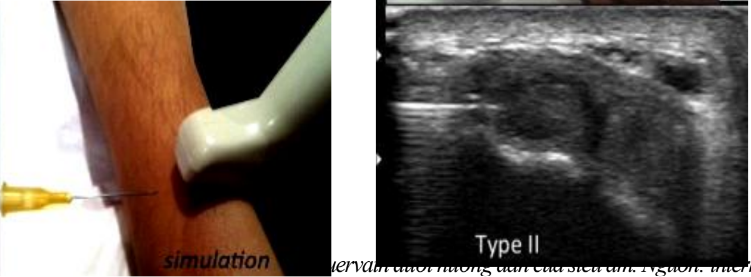

- Siêu âm xác định vị trí cần tiêm: hình ảnh cắt ngang qua vùng dưới mỏm trâm quay thấy được gân dạng dài và duỗi ngắn ngón cái

- Tiến hành chọc kim qua da tiến sát vào bao gân dưới mỏm trâm quay, hướng kim đi song song với đầu dò và vuông góc với chùm tia siêu âm và đồng thời quan sát trên màn hình. Khi kim vào đúng vị trí tam giác ở phía bên trái của trung tâm màn hình thì tiến hành tiêm thuốc. Sau đó rút kim.